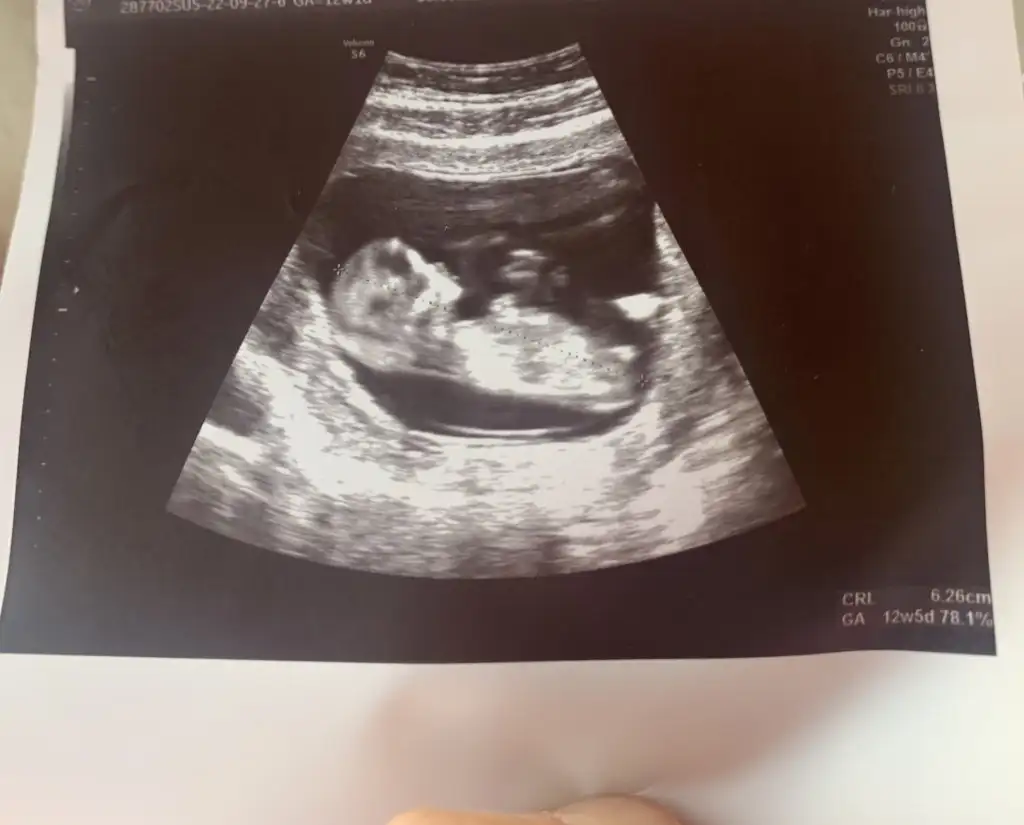

kızlar bir de benim bebise bakar misiniz.

Bana da cevap verir misiniz lutfen. Doktorum emin olmak icin alttan muayene etti kiz kesinlikle dedi ama bu nub teorisi kafami karistirdi bana yardim eder misiniz. Hepimiz saglikla kucagimiza alaim insallah.